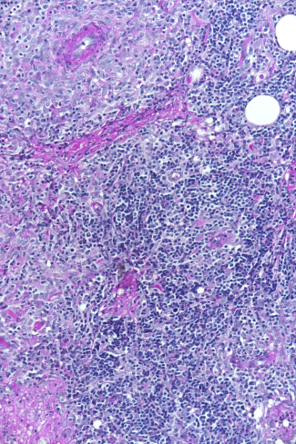

Mikroskopische Aufnahme des Gewebes - geringe Vergrösserung. Mikroskopische Aufnahme des Gewebes - starke Vergrösserung. Bei Aufnahme: Dr. U. Hetzel den dunklen Punkten handelt es sich um Entzündungszellen. Aufnahme: Dr. U. Hetzel

Das Krankheitsbild von Balu ist sehr unüblich. Nicht zuletzt muss selbst bei einem so jungen Hund auch an Hautkrebs gedacht werden, weshalb wir uns zur Entnahme von Gewebeproben unter einer kurzen Narkose entscheiden. Der Gewebebefund ist ebenfalls unüblich: Der Pathologe diagnostiziert einen bestimmten Typ einer entzündlichen Veränderung der Haut (Dermatitis). Eine erweiterte Gewebeuntersuchung weist nach, dass der Hund nicht an einer Leishmaniose leidet - diese parasitäre Krankheit könnte nämlich ein ähnliches Bild verursachen. Abschliessend wird also die Diagnose einer "pyogranulomatösen Dermatitis/Adnexitis" gestellt.